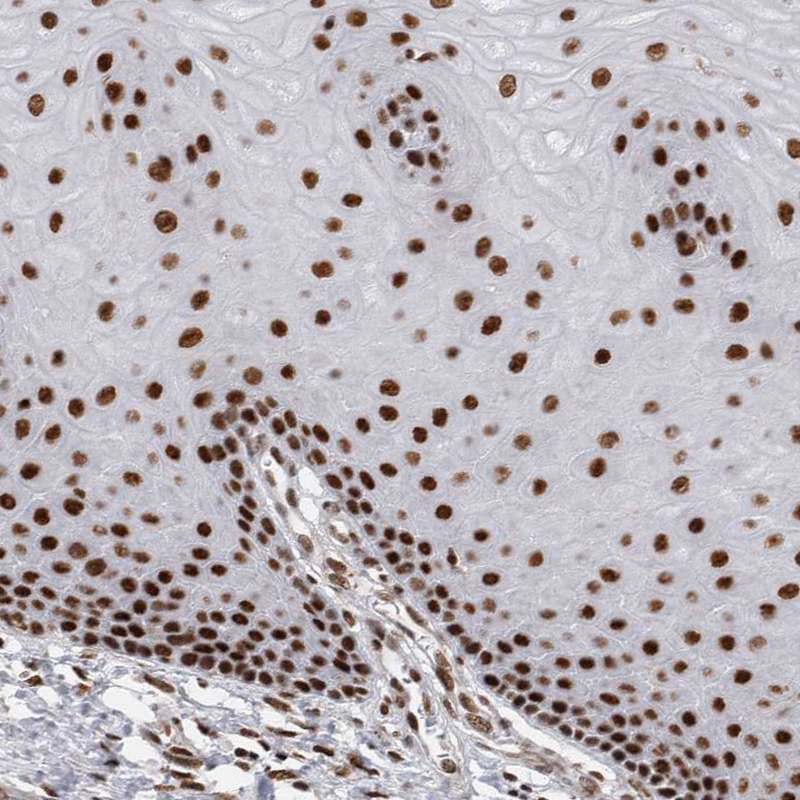

Immunohistochemical staining of human cervix, uterine shows strong nuclear positivity in squamous epithelial cells.